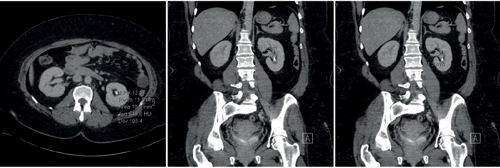

Figure 1a. 650HU, lower pole stone with a wide (11mm) and short (11mm) infundibulum.

The maximum SSD varies according to the lithotripter in use and its specific focal length; but studies generally point to an SSD<10cm as appropriate. Although ESWL can treat (i.e. fragment) stones in all calyces, those within the lower pole have the lowest rate of clearance (25%). The intra-renal anatomy affects this further, with a wide (>5mm), short (<10mm) infundibulum, with a shallow infundibulo-pelvic angle (>70o) allowing better clearance of fragments than if the stone is at the end of a tight, long infundibulum.